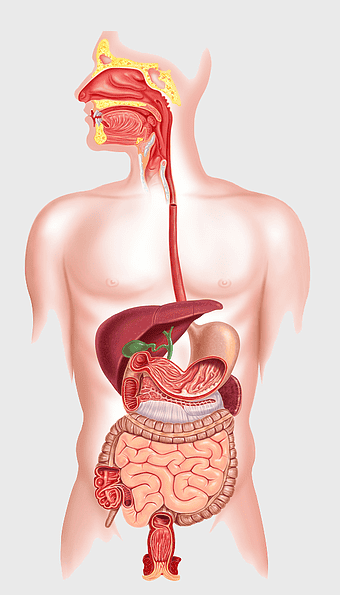

human digestive system, gastrointestinal tract anatomy, liver function, stomach and intestines, digestive health, internal organs diagram, human body systems -